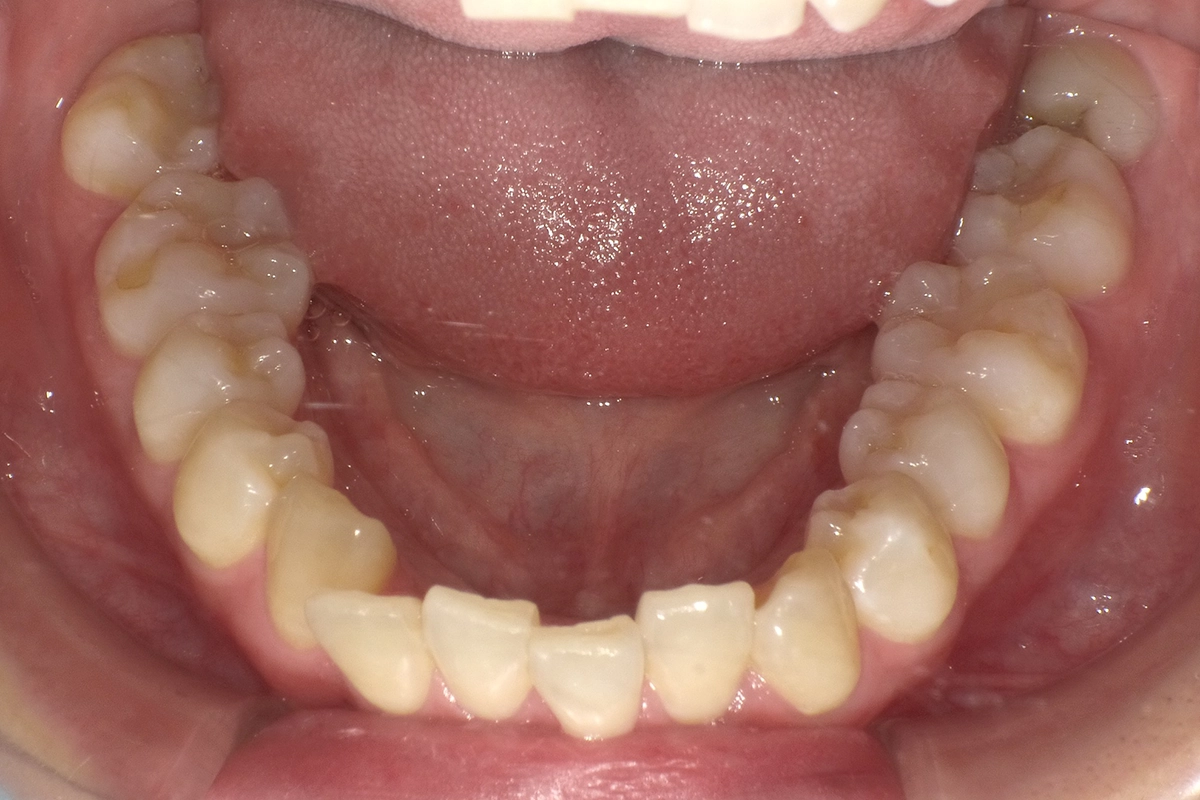

下の歯並び

下の前歯がガタガタして、歯並びが整っていないのが分かります。これが患者様の一番のお悩みでした。

小学生の頃、ワイヤー矯正していたが、徐々に後戻りしてしまい、今のようなガタガタした歯並びになったそうです。

下の歯

下の歯は大きく変化しました。歯並びのガタガタが綺麗に改善されています。